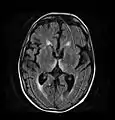

Axial MRI FLAIR image showing hyperintense signal in the mesial dorsal thalami, a common finding in Wernicke encephalopathy. This patient was nearly in coma when IV thiamine was started, he responded moderately well but was left with some Korsakoff type deficits.